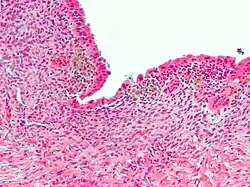

Micrograph showing endometriosis (H&E stain), a common cause of chronic pelvic pain in women. | |